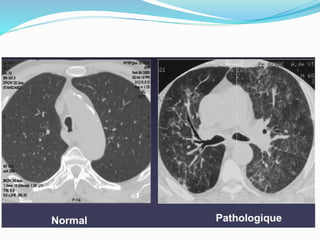

PNEUMOTHORAX

2e question : pneumothorax ?

 Un petit pneumothorax : peut être difficile à voir.

 Radioghraphie thoracique debout : visibilité la

plèvre viscérale, région de l`apex pulmonaire, pas de

vaisseaux entre cette ligne et la paroi thoracique.

 Radiographie thoracique couchée : l`air

intrapleural a des localisations différentes. La partie la

plus haute située au niveau de la base pulmonaire

(chercher l`hyperclarté de la base droite, cul de sac

costo-diaphragmatique latéral, une coupole

diaphragmatique trop bien visualisée).

Scanner plus sensible que la

radiographie standard

Traumatisme du thorax ou

polytraumatismes ++